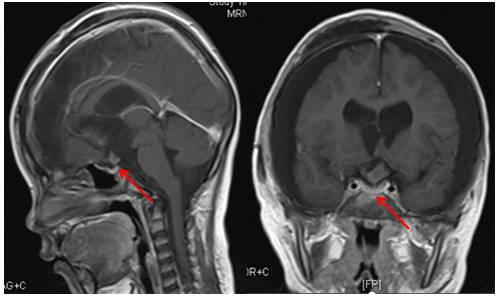

术前MR检查显示,鹏鹏鞍上区颅咽管瘤挤压垂体(左图),颅咽管瘤引起梗阻性脑积水(右图)

颅咽管瘤切除术后MR检查显示,鹏鹏垂体结构受损